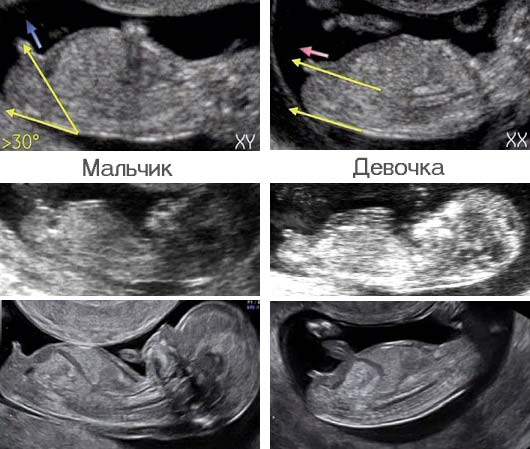

Jess, ага, сегодня проснулась и мутит сильнее 🤢 День на день не приходится С приездом вас ! Отдыхайте и наедайтесь вкусняшек Спасибо, Анют. Краба уже поела) Завтра икру буду))) Они её тут не едят, я сама ем всё))) За всех) Как сказал мне врач: «такое уже не отвалится» и повернув ко мне экран показали все части мужского достоинства моего мальчика 🤣 Я конечно мало что поняла, но что-то там торчало однозначно )))) Вот посмотри, разницу видишь?)  Мне в частной клинике тоже обещали анализы чуть ли не на следующий день Меня это очень смущает, честно. Неужели такая крутая клиника, что своя лаборатория с оборудованием для генетических исследований? Да уж, не простая дорога ( Ну теперь отдыхайте и готовьтесь к встрече Нового года! Уже пытаемся) Меня тут откормить пытаются🙈 Отредактировано: Jess в 30 дек 2018, 20:39

0llich, что за депрессивные мысли? Оставь это и гони их прочь от себя! Только позитивный настрой и вера в лучшее! один процент веры остался...только один процент из ста...  ...завтра утром в инвитро сдаю хгч...к обеду обещают результат...посмотрю динамику с позавчерашним результатом... Вот посмотри, разницу видишь?) вот я тоже как раз об этом угле))) а не по *винтику*), по которому типа определяют пол Отредактировано: 0llich в 30 дек 2018, 20:52

Девочки, у меня к Вам вопрос - мне ставят гестоз, сахар 5,2, пересдавала дважды! Но при измерении глюкометром дома (и на тощак, и после еды) показатели в пределах нормы! Что это - кипишь на пустом месте в ЖК или гестоз так легко уходит при специализированной диете? Так норма вроде до 6. У меня 4.9, сказали всё хорошо. Это я даже не готовилась к сдаче. Я бы попросила переслать анализ и одновременно с же сдала в другом месте, плюс глюкометр ом прям там. И показала врачу. Я с узи. КТР 19,5 мм, сердцебиение отчетливое. Сколько ударов не стали считать , чтоб не навредить ребёнку доплером Гм.. а причем тут Допплер? УЗИ фиксирует сердцебиения ритм на экране, они без допплера замеряют же. Ну это утопия... С хорошим УЗИ!!!! как здорово Анют! как отрадно, что у тебя все отлично! .....а я все больше теряю надежду(....так хорошо ктр у твоего малыша подрос ттт...у меня наверное и правда все плохо(...я тоже уже рассчитывала по узи на такие значения Рано терять надежду. Аппараты разные, узист разные. Ты на поддержке? Может её не хватает? вот я тоже как раз об этом угле))) а не по *винтику*), по которому типа определяют пол